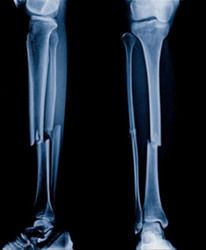

Broken or fractured bones are one of the most common injuries in any kind of accident, ranging from vehicle crashes to slips and falls on the job. These types of personal injuries often require extensive medical treatments and therapies, which can become overwhelmingly expensive. Through a negligence lawsuit, the victim can recover medical costs and receive compensation for pain and suffering.

Virtually any type of trauma can cause fractures or broken bones. Depending on the situation, age, and overall health of the client, broken bones can be mild or severe. The three primary types of bone breaks include:

- Complete Fractures: This type of fracture occurs when the bone breaks in two.

- Compound Fractures: Also called an open fracture, a compound fracture occurs when the bone breaks through the skin.

- Simple Fractures: This type of break includes stress, oblique, hairline, impacted, and comminuted fractures.

The more severe the trauma, the more extensive the medical treatment can be. In some cases, a fracture is so catastrophic that it requires a surgical procedure in which the doctor repairs the break with internal rods, screws, and plates. This procedure is called an open reduction internal fixation.